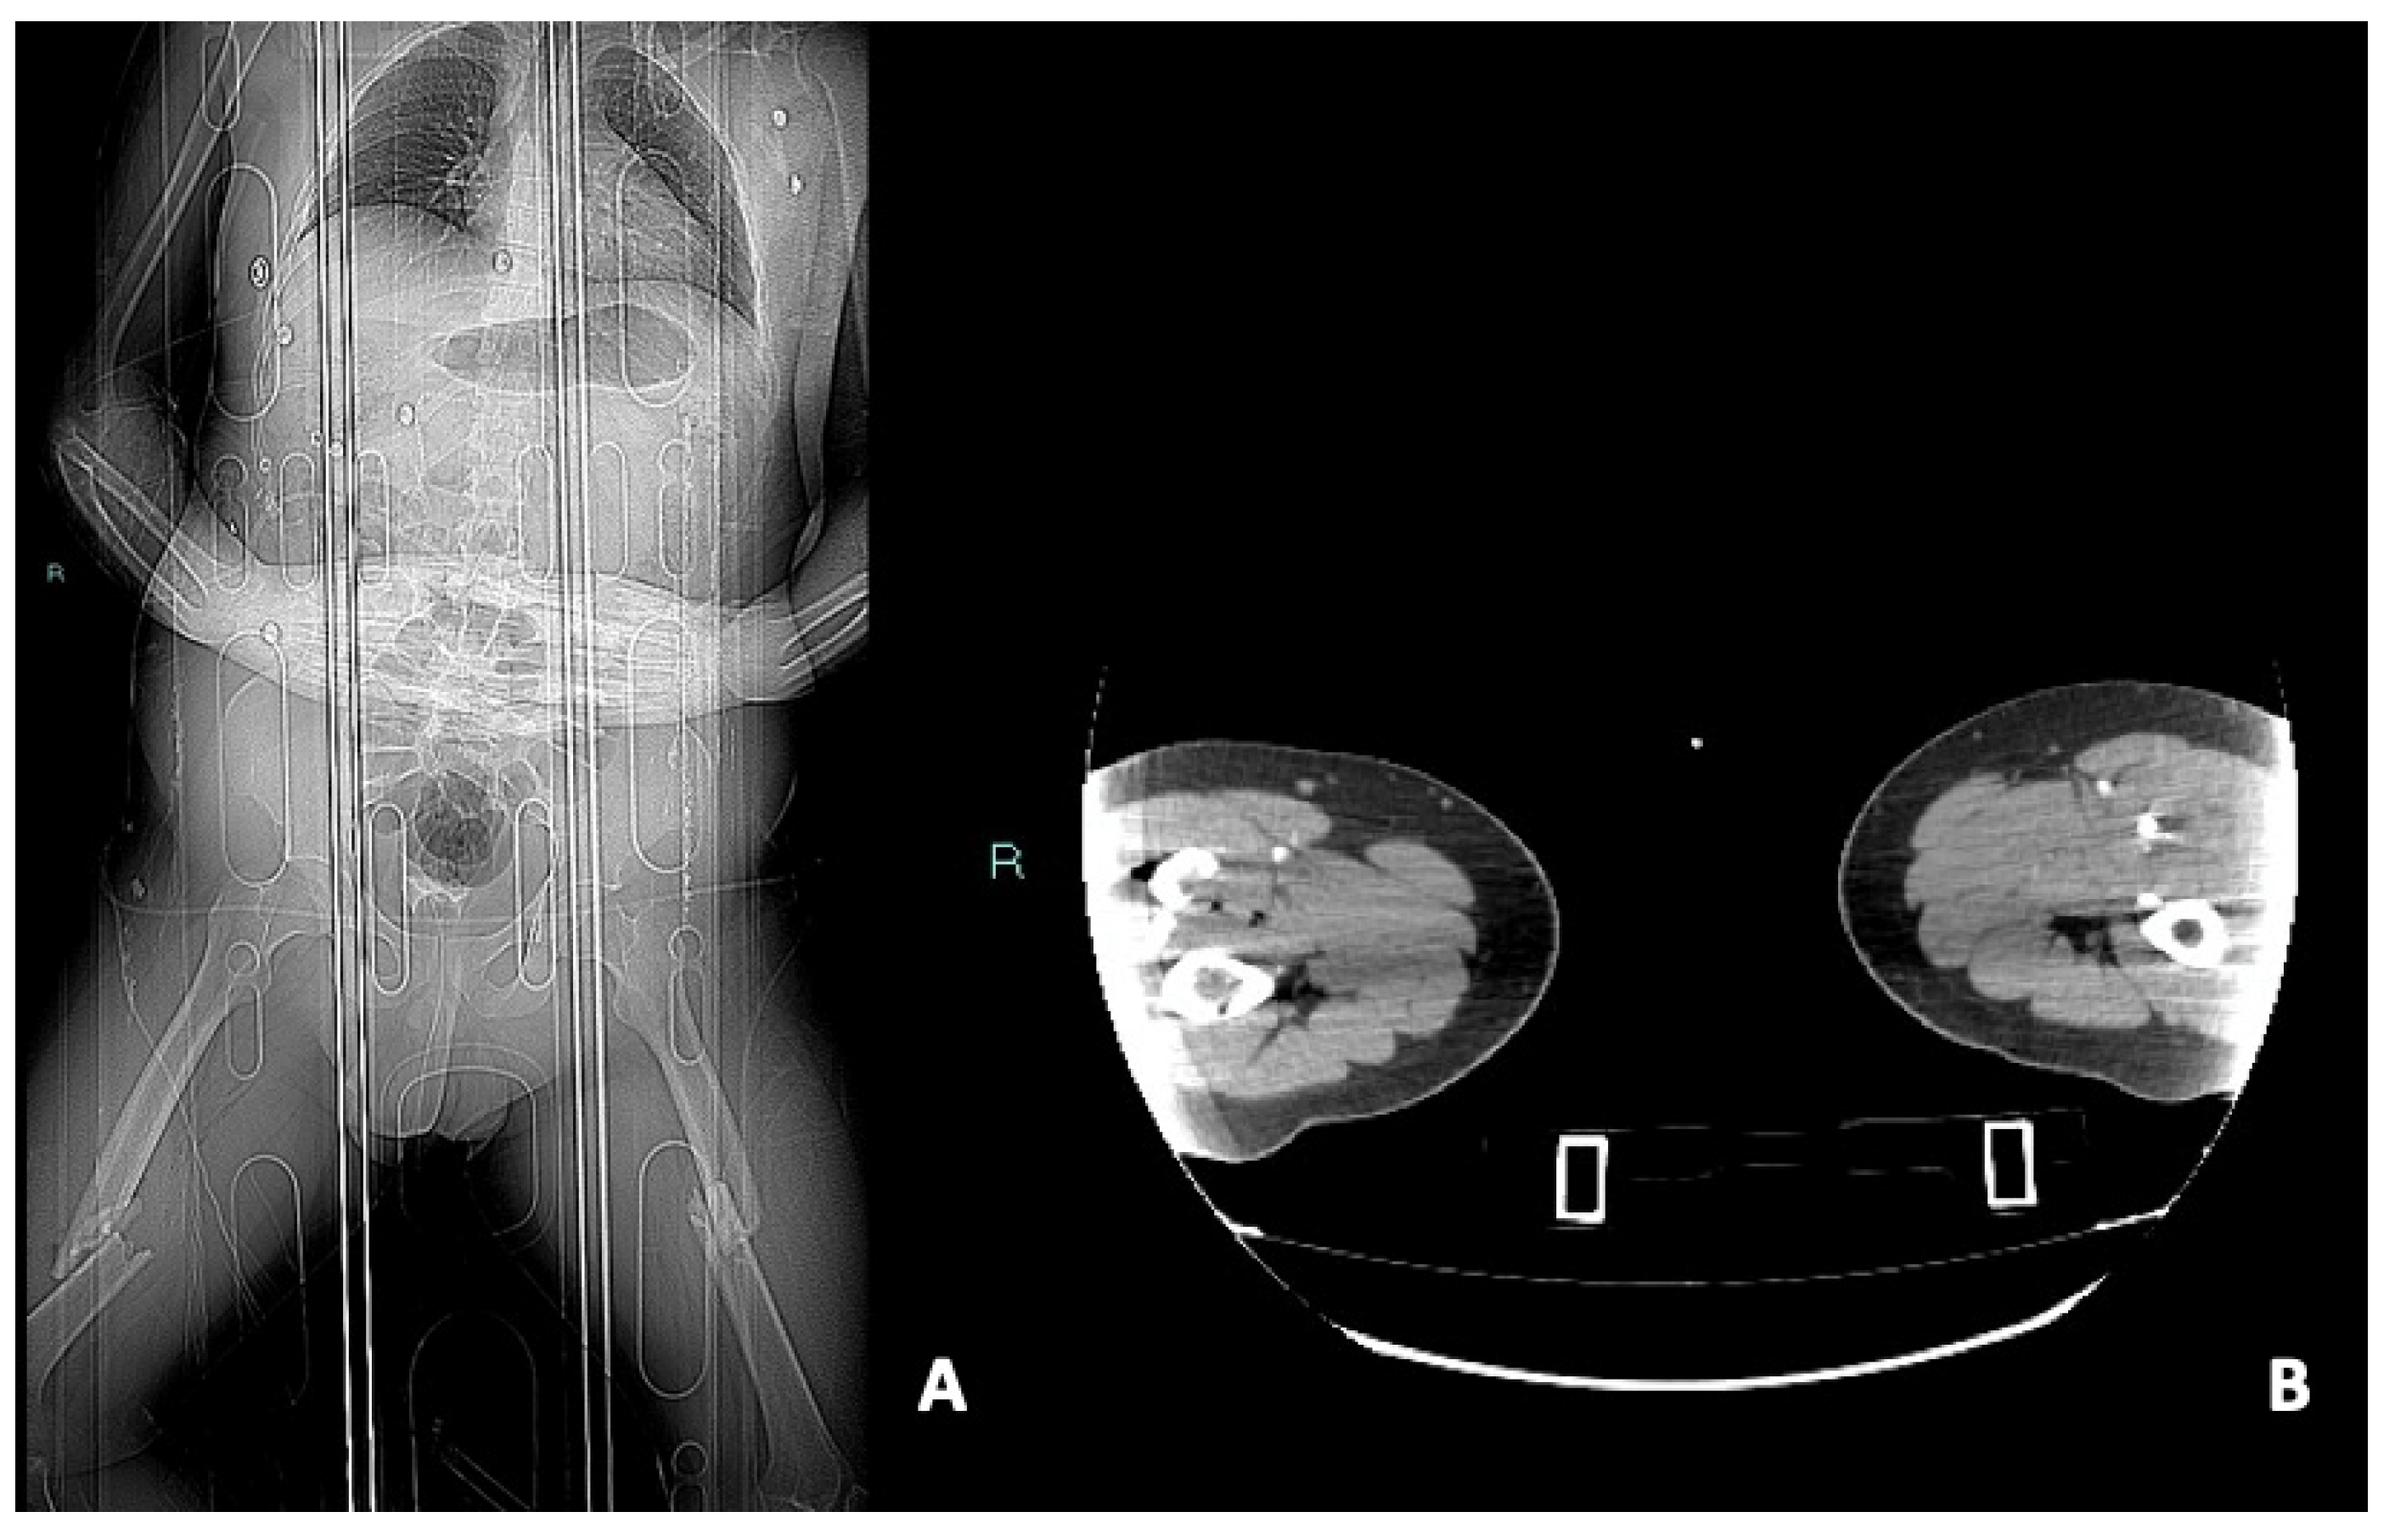

- Pseudoaneurysm is caused by focal arterial wall tear involving intimal and medial layers, and represents a collection of blood contained only by the adventitia layer or surrounding tissue [5,56,59]. It appears as an outpouching sac with a round and smooth margin in continuity with the arterial adjacent lumen (Figure 4). Pseudoaneurysm bleeding appears as irregular, lobulated perilesional contrast blush [65,68]. Pre-exiting calcification or pseudoaneurysm should be differentiate form active bleeding; delayed phase acquisition can be useful because in active bleeding the contrast extravasation dissipates along tissue planes instead pseudoaneurysm and calcification remain stable [60,67].